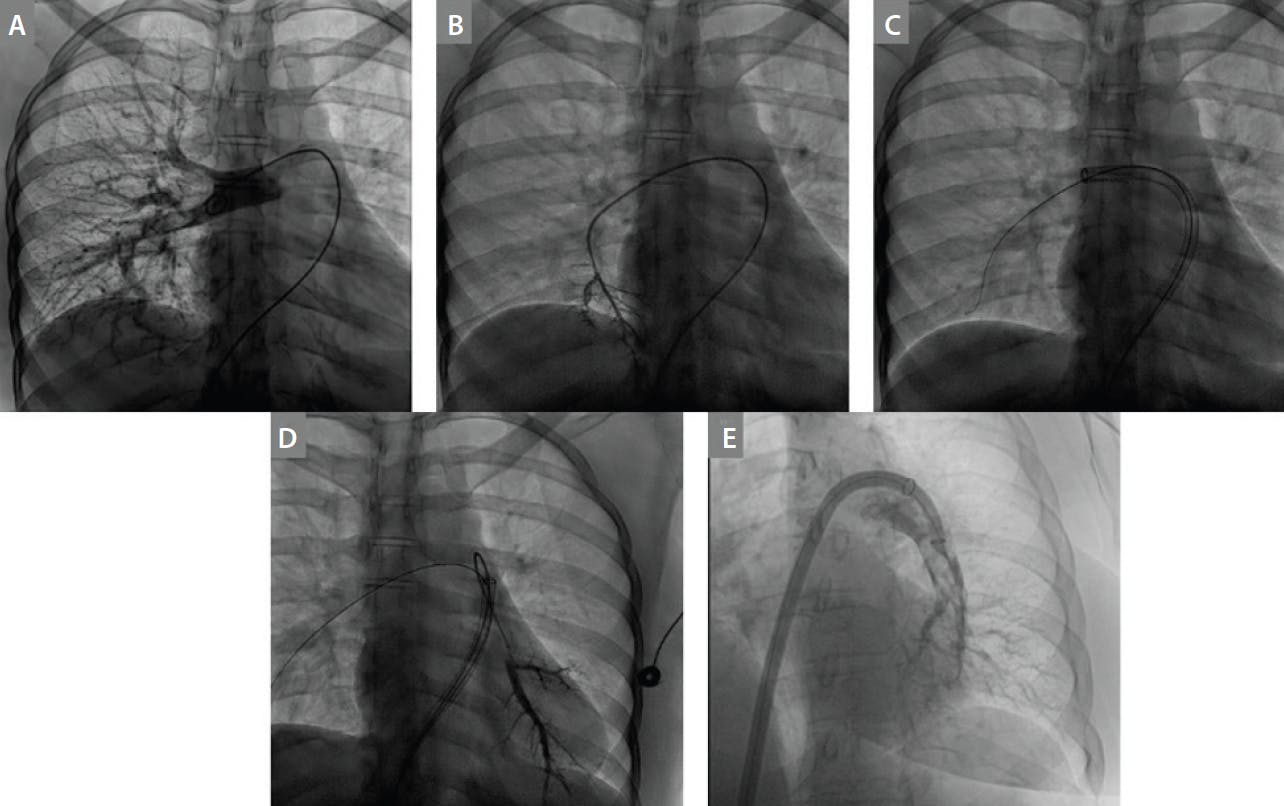

Access to the pulmonary vasculature is achieved via a pigtail catheter or a 7-F balloon-tipped catheter placed in the main PA. Then, a pulmonary angiogram is obtained to visualize the clot(s) and distal vasculature and to select a lobar branch into which a stiff wire can be placed (Figure 2A). A Hi-Torque Supra Core guidewire is placed through the pigtail catheter or balloon-tipped catheter, and the right PA is wired. Depending on where the thrombus is located, the guidewire is placed in either a posterior or anterior lobar branch. Then, a 125-cm multipurpose A (MPA) catheter is inserted over the Supra Core; using a 10-mL syringe, contrast is injected, making sure that the catheter is not in a very small branch that would be susceptible to traumatic injury (Figure 2B). Next, a 1-cm-tip, 260-cm-length Amplatz Super Stiff wire is delivered through the MPA catheter into the lobar branch.

Figure 2. The Inari FlowTriever system for use in acute PE. Pulmonary angiography of the right main PA and associated lobar branches (A). Piggyback system of a 125-cm, 5-F MPA catheter inside a 100-cm, 6-F JR4 guide catheter (B). The Triever24 over an Amplatz Super Stiff wire (C). The Triever24 switched to the left lung (D). The Triever20 Curve catheter inside a Triever24 (E).

When the 0.035-inch Amplatz Super Stiff guidewire is in place, the initial short sheath is replaced with a 24-F sheath. Inari’s own 24-F sheath, the Intri24 introducer sheath (Inari Medical), or the 24-F Gore DrySeal sheath can be used. The Triever24 aspiration catheter is then advanced into the left or right main PA, and aspiration is performed using the retraction aspirator device (Figure 2C). Using the FlowSaver device (Inari Medical), aspirated blood can be filtered to remove clot and then reinfused back to the patient via the access sheath to minimize blood loss. It incorporates a 40-µm filtration system to filter the aspirated blood, which is collected into a 60-mL collection syringe. The blood can then be injected back through the sheath. The equipment is removed when pulmonary angiography—which can be performed through the aspiration catheters—shows improvement in flow and there is improved hemodynamics.

If necessary, the nitinol mesh disks (in the first- and second-generation FlowTriever) can be advanced through the aspiration catheters to break up the clot prior to resuming aspiration. The aspiration catheter can then be withdrawn into the main PA, and an 0.035-inch Hi-Torque Supra Core guidewire can be advanced into the opposite PA and into a lobar branch. Using a multipurpose catheter, the wire can be exchanged for a 1-cm-tip Amplatz Super Stiff guidewire. The dilator of the aspiration catheter is then used to advance the catheter into position to proceed with aspiration (Figure 2D). If the wire is difficult to advance into the lobar branches due to lack of catheter support, the MPA catheter can be “piggybacked” through a 6-F Judkins Right 4 (JR4) guide catheter (Figure 2B). We have found that this catheter system helps provide enough support to advance the stiff wires distally. To increase drive support, another option is to include a long sheath such as a 6-F Pinnacle Destination sheath (Terumo Interventional Systems) with the piggyback system of JR4 and MPA catheters.

Changing the direction in which the aspiration catheter faces often helps improve the ability to suction clot from the vasculature. Biplane imaging can assist in determining the position of the catheter with regard to the thrombus location. If changing the location and direction of the catheter does not improve the success of aspiration, another catheter can be inserted through the 24-F system. The Triever20 curve is designed in such a way that it overcomes the phenomenon of rainbow effect on the left and has better torquibilty and negotiability for difficult anatomy. The Triever16, due to its smaller size, allows access to more distal clot on either side (Figure 2E). If the vessel size dictates the use of a smaller catheter, then the Triever16 aspiration catheter can also be delivered through the Triever24 catheter.